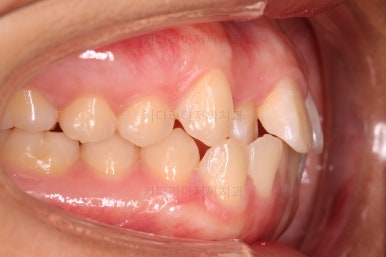

초진 시 입안의 모습이에요. 치열이 많이 나쁜 편은 아니고 앞니쪽이 조금 삐뚤어져 있네요.

특히 윗니 작은 앞니 하나가 아랫니보다 안으로 쑥 들어가 있어서 옆에 있는 송곳니가 덧니처럼 보여요.

라고 대부분 말씀 들을 하시지만 실제로 입 안을 보면 송곳니(덧니)가 많이 튀어나가 있기 보다는 옆에 있는 작은 앞니가 쏙 들어가서 상대적으로 튀어나와 보이는 경우가 대부분이에요.

이래나 저래나 덧니처럼 보이는 건 마찬가지이고, 공간을 확보하여 가지런하게 해줘야 하는 것도 사실이지만요.